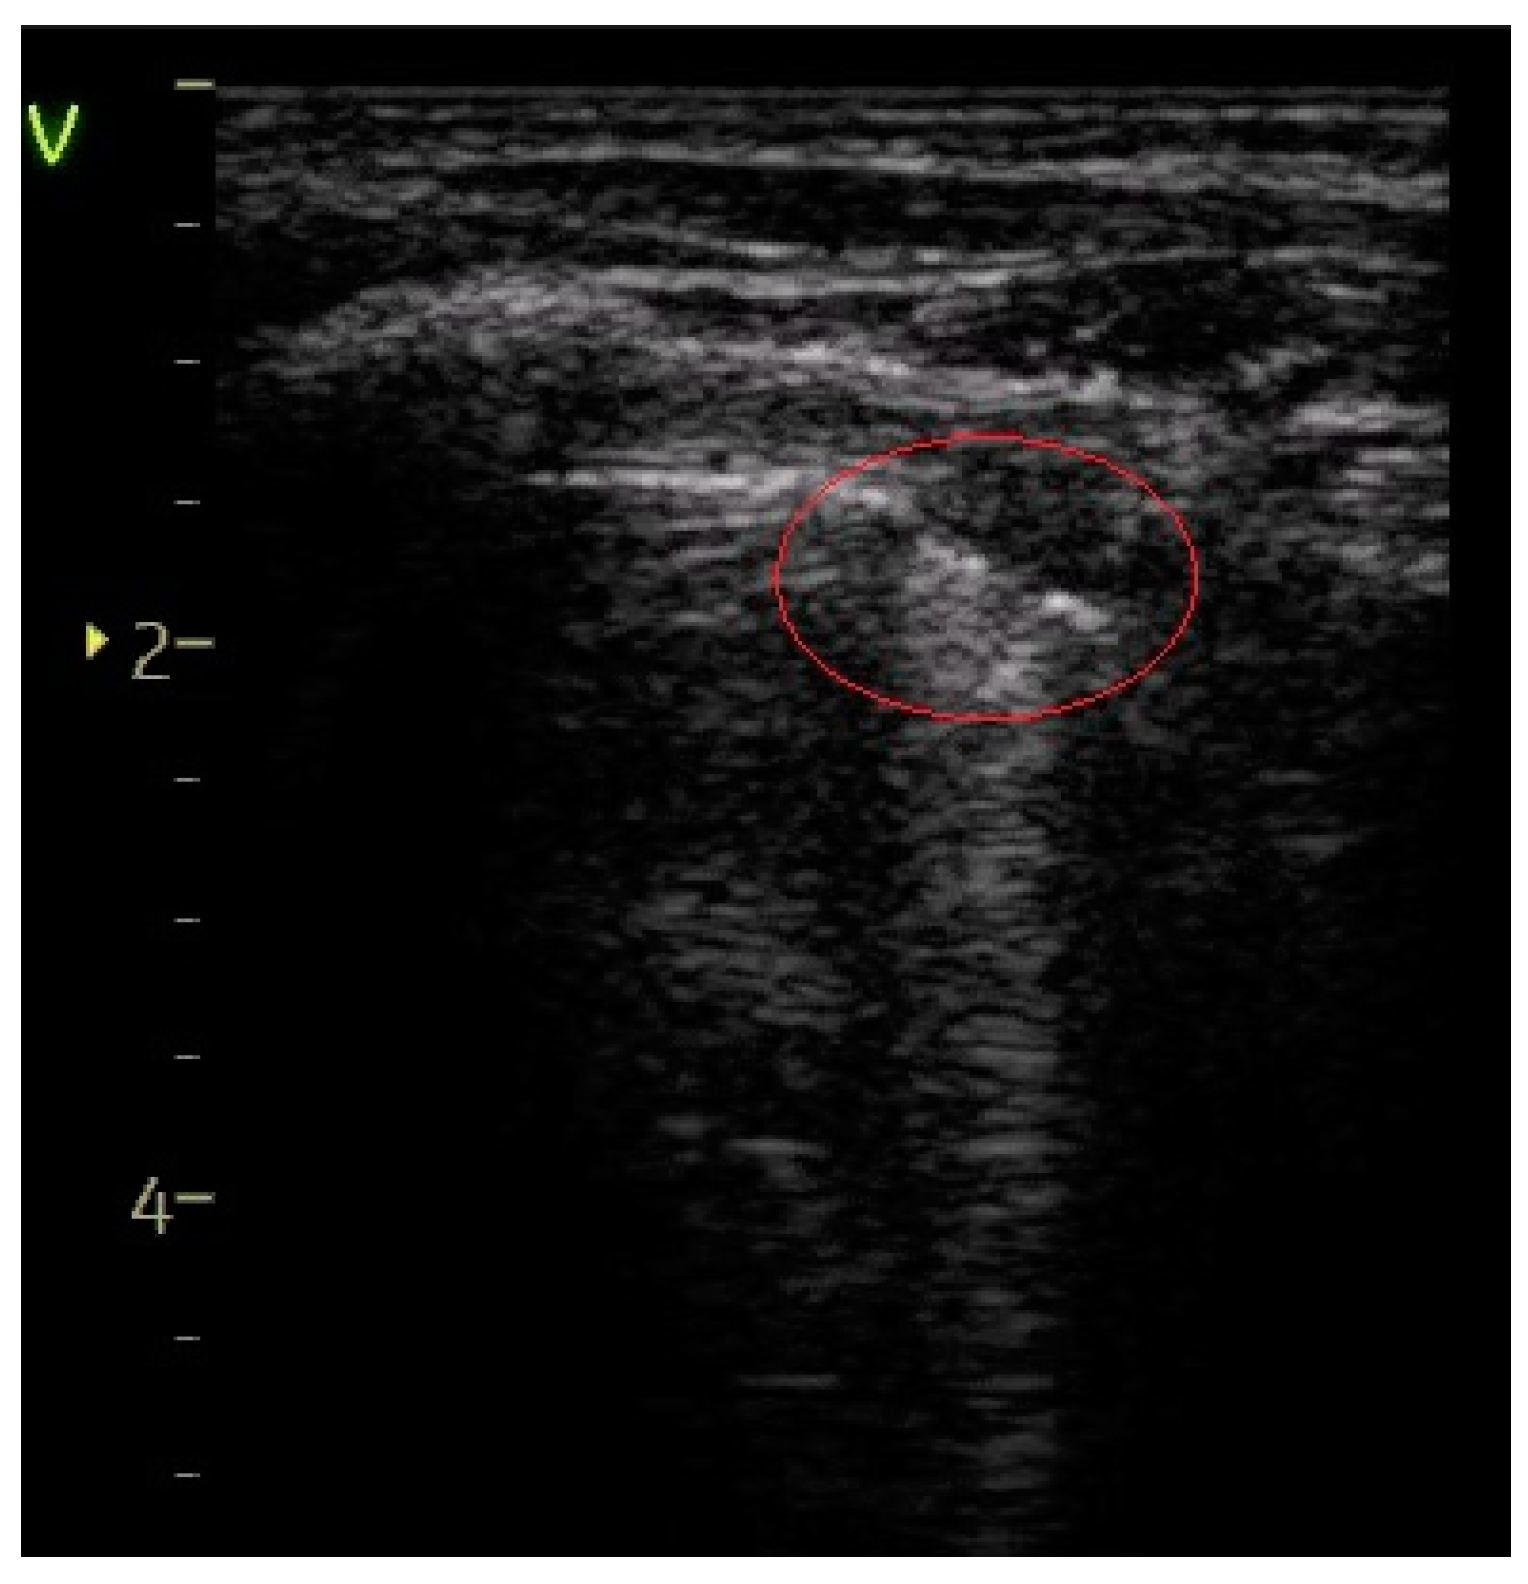

- A score of 2 was allocated for the presence of coalescent or merging B-lines, a ‘white-lung’ appearance, or small peripheral consolidations smaller than 1 cm.

| Subpleural consolidation of < 1 cm—Figure 6 | 15 (20.27%) | 9 (81.82%) | 61.55% | 17.69 | <0.0001 |